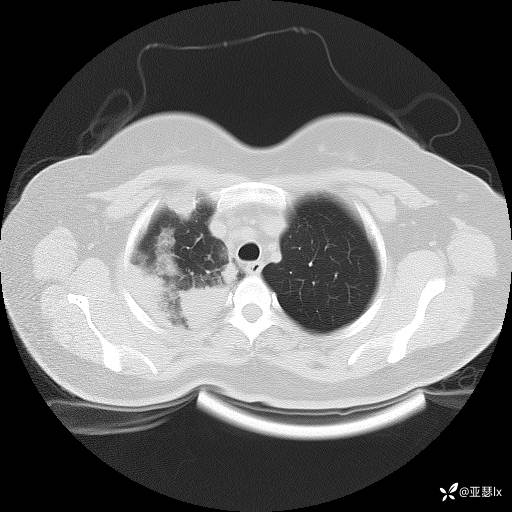

影像学:

初步诊断:社区获得性肺炎

诊断依据:1.社区发病;2.病史及体征:咳嗽、发热等急性感染表现;查体:右肺可闻及湿罗音,触觉语颤增强;3.实验室检查:感染指标明显升高;影像学:右肺实变影。